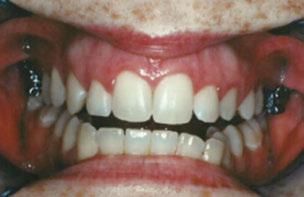

Figure 2: Initial lower occlusal

Figure 1: Initial center photo

This case involves a 13-year-old female patient with a complex malocclusion that includes multiple dental and skeletal issues. During the initial consultation, clinical evaluation showed severe maxillary crowding along with generalized spacing in the mandibular arch. The patient’s occlusal relationships were asymmetric, with a Class I molar relationship on the right side and a Class II molar relationship on the left. Notably, an anterior crossbite was observed, further complicated by a narrow, V-shaped maxillary arch — a common presentation that often exacerbates anterior-posterior discrepancies and limits functional occlusion. The patient also demonstrated poor oral hygiene, which is a key indicator of an indirect bonding system that does not reduce excess flash. ODB is superior in flash reduction, by being able to remove excess adhesive from three sides of the bracket instead of competitors who only remove adhesive from one side of the bracket. The presence of adhesive around brackets contributes to surface roughness which leads to plaque accumulation.1 Flash reduction will be very important for every patient’s orthodontic success (Figures 1-3).